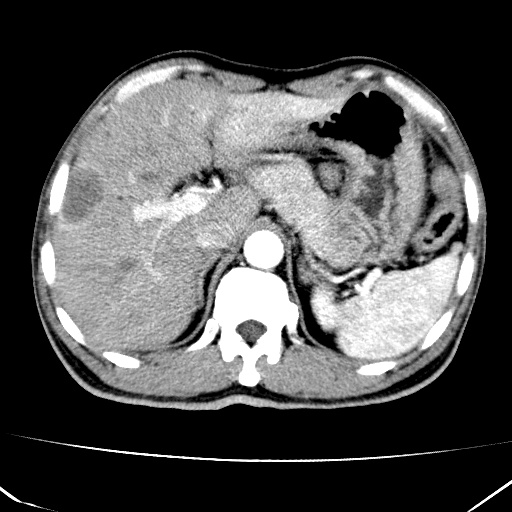

标题: CT17975:请求会诊。男、57岁。上腹部胀痛2天。临床诊断:糜 [打印本页]

标题: CT17975:请求会诊。男、57岁。上腹部胀痛2天。临床诊断:糜

肝脏多发类圆形低密度影,考虑肝脏转移瘤,肝胃韧带一淋巴结肿大,原发?胃癌?

考虑胃癌肝脏转移可能性大。

考虑胃癌并肝脏及腹膜后淋巴结转移;不排除淋巴瘤。